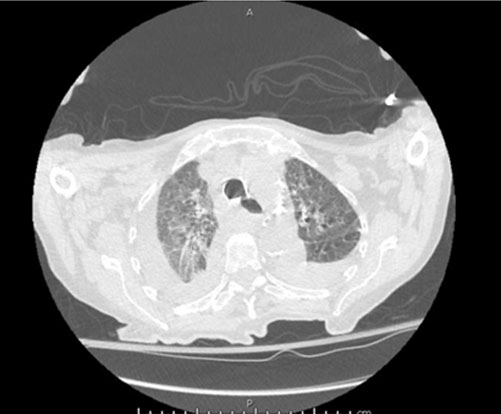

She stated that her shortness of breath was exacerbated by exertion and associated with orthopnea, paroxysmal nocturnal dyspnea, and swelling in her lower extremities. She denied any recent history of trauma, symptoms of respiratory infection, and had not had any recent surgery. After a chest X-ray was completed and demonstrated a small left and moderate right pleural effusion (Figure 1 and Figure 2), she was given a trial of furosemide. Five days later, she returned to the Cancer Center stating that her symptoms had not improved. At that time, she was noted to have a SpO2 of 85% on room air and rales in the bilateral lower lung fields. She was immediately referred to the hospital for admission.

Upon arrival in the hospital, she was afebrile, normotensive, with improved O2 saturation on nasal cannula. Her physical examination was notable for atrial fibrillation, decreased breath sounds in the right lower, left middle, and left lower lung fields with accompanying rales. Her labs revealed white blood cell (WBC) of 34.25 × 103/uL with 82% lymphocytes, hemoglobin of 11.0 g/dL, platelets of 106 × 103/uL, creatinine of 1.13 mg/dL, aspartate aminotransferase (AST) of 46.0 U/L, alanine aminotransferase (ALT) of 11.0 U/L, alkaline phosphatase 120 U/L, and pro-brain natriuretic peptide (pro-BNP) 2823 pg/mL. Computed tomography of the chest (Figure 3 and Figure 4) demonstrated large right and moderate left pleural effusions with near complete and partial atelectasis with marked axillary lymphadenopathy. She was started on diuretics for suspected pleural effusion secondary to congestive heart failure.

Figure 3: Coronal view of CT chest without intravenous (IV) contrast showing large right and moderate left pleural effusions with associated atelectasis and marked axillary lymphadenopathy.

Figure 4: Axial view of CT chest without IV contrast showing large right and moderate left pleural effusions with associated atelectasis and marked axillary lymphadenopathy.